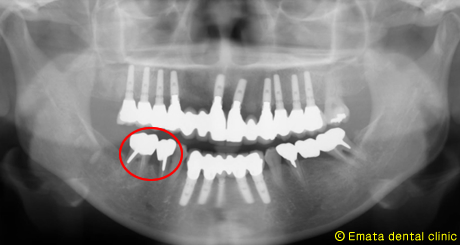

インプラントにキヤップをつけ、一回法です。 |

術後 |